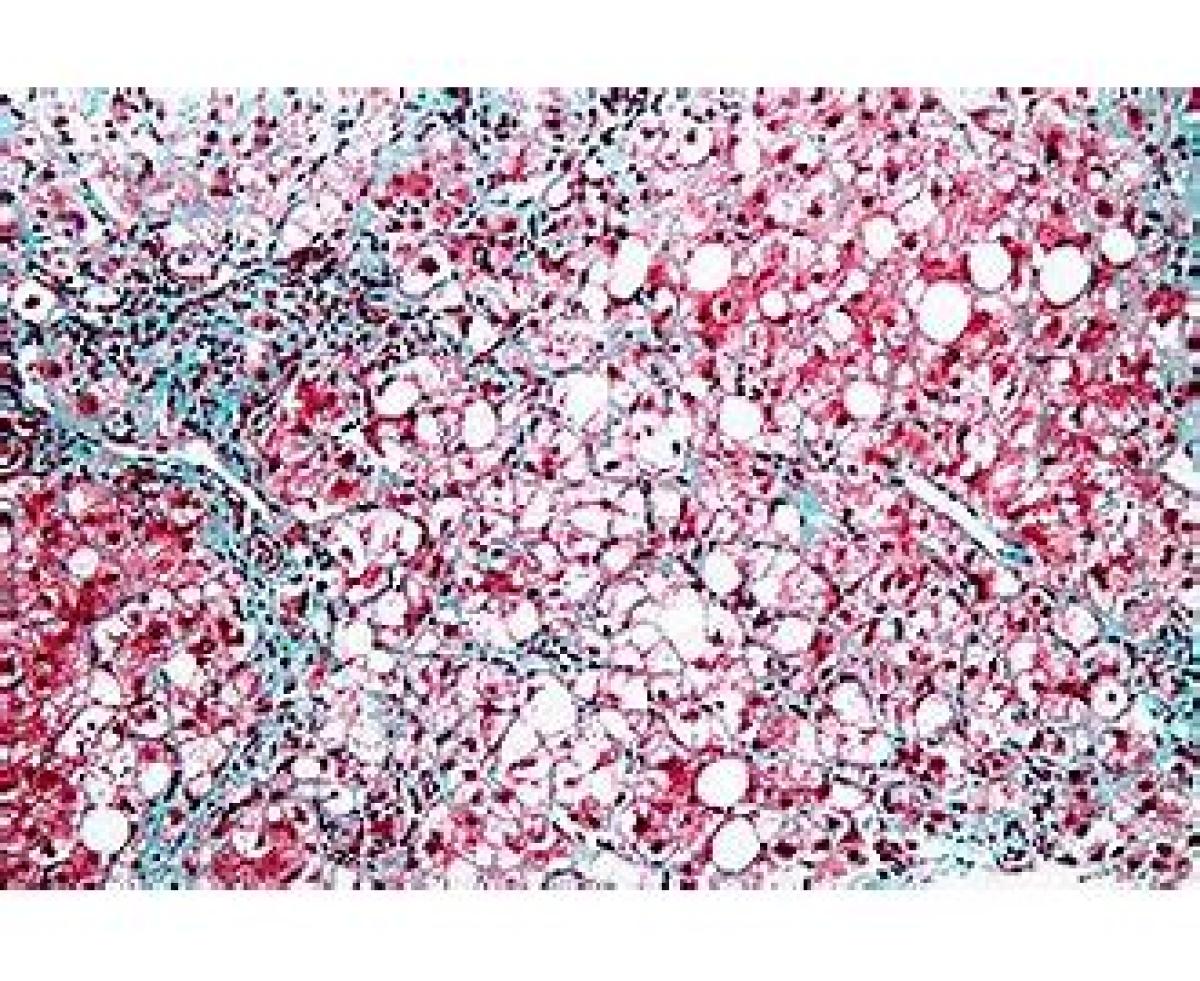

مخفف NASH

Non-Alcoholic SteatoHepatitis

التهاب کبدی غیر الکلی